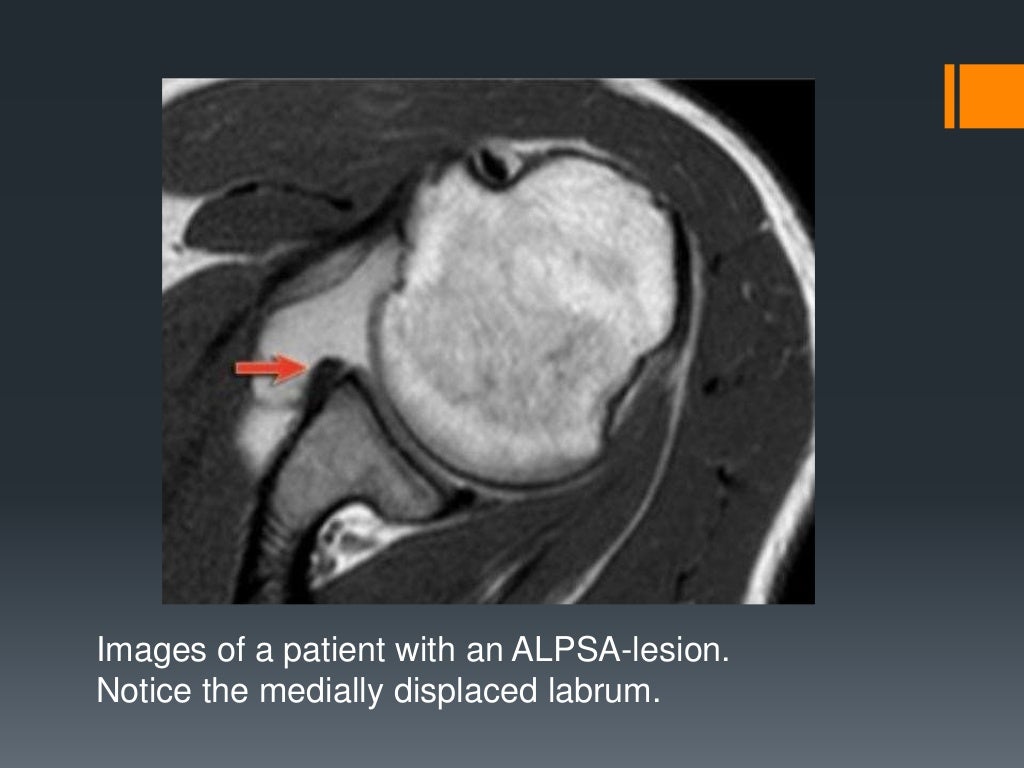

From www.slideshare.net